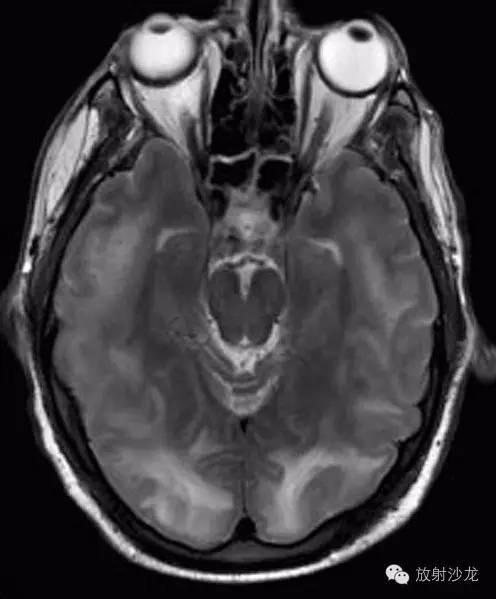

Virchow-Robin (VR) spaces也有称之为血管周围淋巴间隙,VRS将血管与周围的脑组织分离开来,是神经系统内的正常解剖结构,约1-2mm,也有个别超过1cm.VRS充满组织间液,而不是脑脊液。直径>2mm的VRS被认为是VRS扩大,还见有巨大VRS、海绵状VRS等。扩大的VRS的特征是边界光滑清楚,呈圆形或线形(由于部位和切面不 同),与穿通动脉的行径相一致,在MRI的T1WI、T2WI和FLAIR序列上与脑脊液信号是相同的。无对比剂增强效应,无占位效应。FLAIR对于区 别VRS和缺血灶非常有用,缺血灶呈高信号区域,而VRS与CSF的信号相同,呈低信号改变。